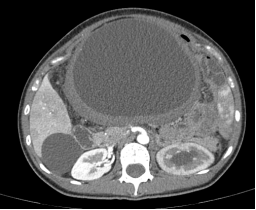

患者张某,31岁女性,因腹胀、腹痛反复发作3年辗转就医。此前已在外院经历4次腹部手术,其中2021年因家族性肠息肉病行全结肠切除术。2022年起,腹部包块迅速增大至25cm×18cm,如同怀胎七月的孕妇,压迫导致进食困难。其家属先后带患者前往北京301医院、北京肿瘤医院等顶尖医疗机构就诊,但因肿瘤与肠系膜血管、十二指肠紧密粘连,切除后可能引发致命性大出血或多器官衰竭,多家医院评估手术风险后选择保守治疗。

2024年10月,饱受折磨的患者抱着最后一线希望来到我院肝胆胰脾外科。入院后检查显示,肿瘤已侵犯约60%的小肠肠管,且包绕肠系膜上动脉分支。党委副书记、院长张俊晶立即启动MDT(多学科诊疗)机制,联合医学影像科、麻醉科、介入治疗科、重症医学科等进行多次联合会诊。

肠系膜纤维瘤病(Mesenteric Fibromatosis)是一种罕见的间叶源性肿瘤,起源于肠系膜或腹膜后纤维组织,占消化道间叶源性肿瘤的0.8%-1.2%,年发病率约0.17/10万。其生物学特性介于良恶性之间,尽管无远处转移倾向,但具有侵袭性生长、术后易复发(5年复发率40%-60%)的特点,被称为“交界性肿瘤”。与遗传因素(如家族性腺瘤性息肉病基因突变)、创伤或手术史(局部炎症刺激)、激素水平(雌激素受体阳性)相关。肿瘤常包裹肠系膜血管(如肠系膜上动脉分支)、肠管及邻近脏器,形成“树根状”粘连,导致手术分离困难。常规CT误诊率达43%,需结合MRI弥散加权成像(DWI)与超声造影才能将准确率提升至89%。肿瘤每增大1cm,主要血管损伤风险增加17%;复发率五年内高达40%-60%。